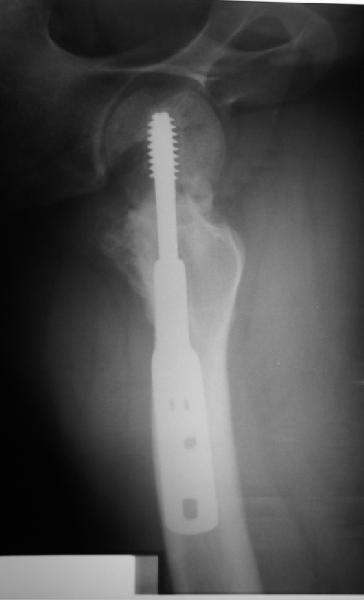

Учитывая возраст больного и качество кости, я однозначно за остеосинтез. Можно обойтись и без остеотомии, линия излома не вертикальная. Возможно с костной аутопластикой для стимуляции. Только отрепонировать хорошо, на представленных снимках, перелом недорепонирован, есть ротационное смещение. Плюс винт биомеханически введен не совсем удачно.

на представленных рентгенограммах прослеживается линия резорбции вокруг введенного винта, что свидетел ствует о нестабильности произведенного остеосинтеза ии отсутствии консолидации перелома. На мой взгляд нужно произвести ркт исследование и выполнить при отсутствии консолидации реостеосинтез с костной аутопластикой. При отсутствии сращения после данной операции остается ввариант с эндопротезированием. Выполнить репозицию несросшегося перелома закрытым способом на мой взгляд не совсем реально, открытая репозиция чревата аваскулярным некрозом. Выполнение вальгизирующей остеотомии считаю нецелесообразным так как это приведет к увеличению давления на головку (за счет натяжения мышц бедра )6 лишенную нормального кровотока приведет к ее коллабированию. С уважением Даниленко Олег.

Уважаемые коллеги! мне кажется, что можно ввести в шейку дополнительно 1-2 спонгиозных компрессирующих винта параллельно опорному винту ДНС - его по видимому заклинило в втулке опорной пластины, что и послужило причиной несращения. Винты дадут дополнительную компрессию, стабилизацию и динамизацию. А протез всегда успеете.